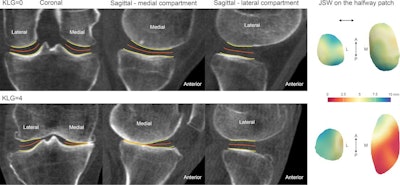

Articular bone surfaces at the femur and tibia from joint space mapping output (yellow) with the halfway surface (orange), alongside joint space width (JSW) displayed on the halfway patches (far right). This is shown for individuals with a radiographic Kellgren-Lawrence grade (KLG) of 0 (top row) or 4 (bottom row), demonstrating robust performance in the extremes of the disease. A = anterior, L = lateral, M = medial, P = posterior. Image and caption courtesy of the RSNA.Also, one patient with a Kellgren-Lawrence grade of 2 had a 24-month change in a patient's 3D joint space width distribution that was beyond the smallest detectable difference across the lateral joint space, according to the researchers.